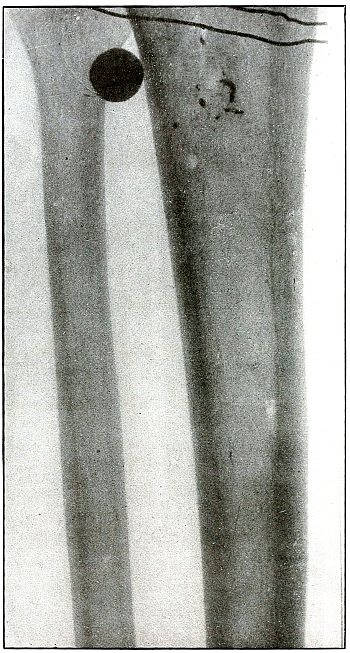

Gunshot fracture, tibia and fibula |

130 |

| 61. |

Gunshot fracture, tibia and fibula |